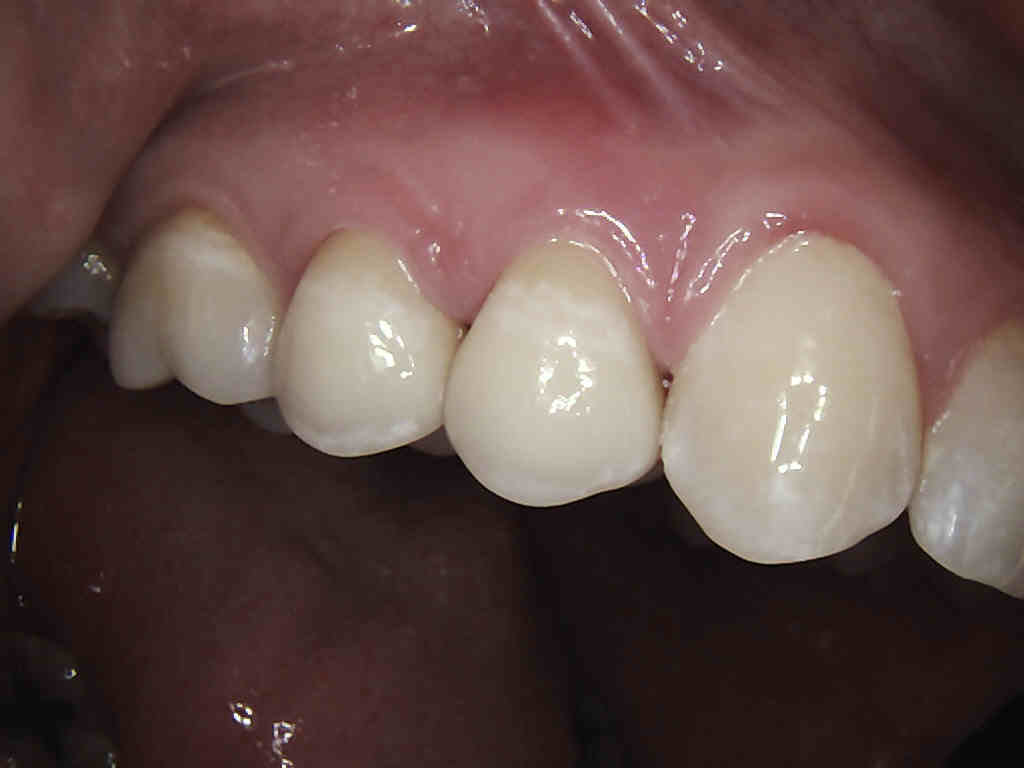

Porcelain crowns and restorations made in one appointment.

We make it a priority to incorporate the latest in dental technology in everything we do at our practice. ...